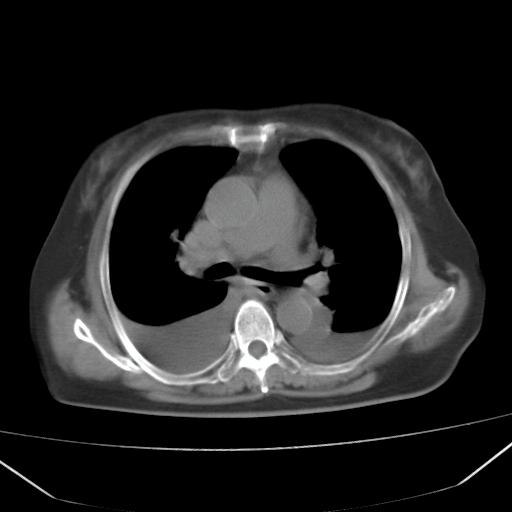

以下是引用liuyue在2008-4-19 22:25:00的发言:[br]先考虑:1.心衰伴肺水肿、双侧胸腔积液、叶间积液、双下肺不完全性肺不张; [br] 2.冠状动脉粥样硬化。

以下是引用lijuanln在2008-4-19 23:05:00的发言:[br]两侧胸腔积液,肺水肿[br]心包积液[br]提示心衰

以下是引用jiangjing在2008-4-20 10:43:00的发言:[br]结合病史支持 冠心病[冠状动脉钙化],心功能不全,肺淤血、肺水肿,双侧胸腔与斜裂积液